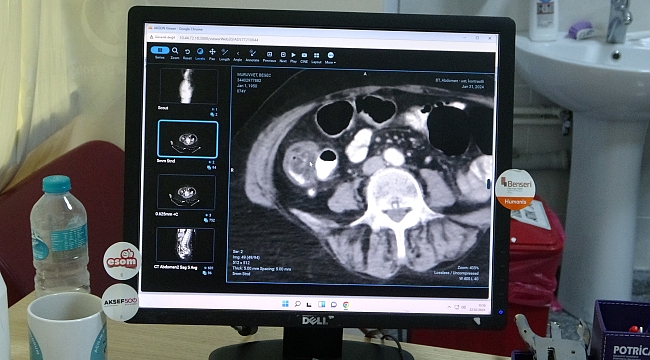

Malatya Eğitim ve Araştırma Hastanesinde görev yapan Genel Cerrahi ve Gastroenteroloji Cerrahisi Uzmanı Dr. Mehmet Güzel, Türkiye’de 2022 verilerine göre yılda 22 bin kişiye kolon kanseri tanısı konulduğunu belirterek, bunlardan yaklaşık 12 binin hayatını kaybettiğini söyledi.

Dünya Sağlık Örgütü'nün verilerine göre, kalın bağırsak kanserinin kalp damar hastalıklarından sonra en fazla ölümlere neden olan bir hastalık çeşidi olduğuna dikkat çeken Genel Cerrahi ve Gastroenteroloji Cerrahisi Uzmanı Dr. Mehmet Güzel, “Kalın bağırsak kanseri kalp damar hastalıklarından sonra Dünya Sağlık Örgütü'nün verilerine göre en fazla ölüm nedeni olarak yer almaktadır. Kanser hastalıkları arasında ise Akciğer, meme, prostat kanserinde sonra dördündü sıklıkta görülmektedir. Türkiye’de 2022 verilerine göre yılda 22 bin kişiye kolon kanseri tanısı konulmaktadır bunların yaklaşık 12 bini vefat etmektedir” dedi.

Hastalığının belirtileri hakkında bilgiler paylaşan Güzel, “Kalın bağırsak hastalığında belirtileri ise tuvalet alışkanlıkları çok önemli yer tutmaktadır. Eğer tuvalet alışkanlığında değişiklik söz konusu ise uzun süre kabızlık ve kana ve kilo kaybı söz konusu ise kalın bağırsak tümörü açısından şüpheli duruma gelmişti. Bu noktada kolonoskopi yapmakta fayda vardır” ifadelerini kullandı.